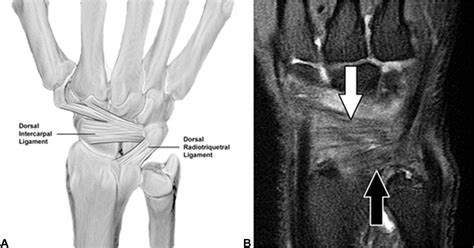

Diagnosing a Scapholunate Ligament Tear involves a combination of physical examination and imaging tests. The diagnostic process typically includes:

• Imaging Tests: X-rays, MRI, and CT scans can provide detailed images of the wrist, helping to confirm the diagnosis and assess the extent of the injury.